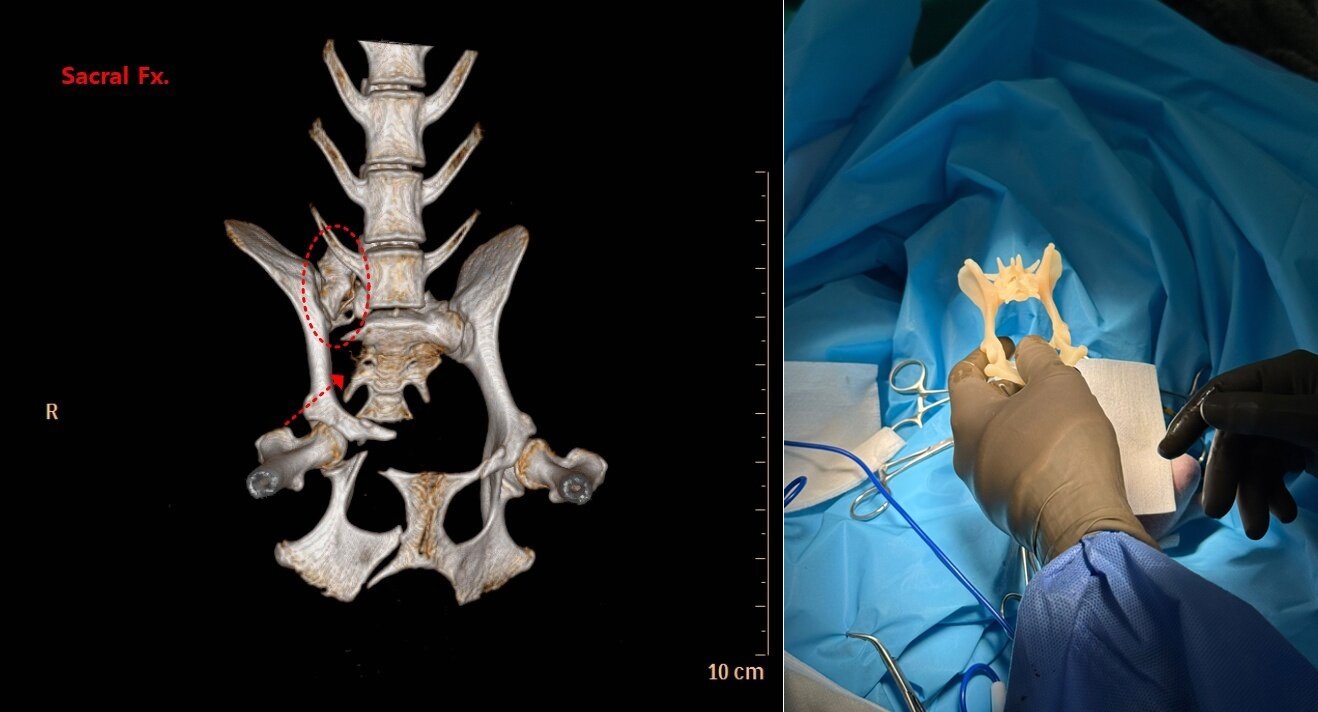

본문 이미지 - 교통사고를 당한 반려견의 CT 검사 사진과 3D 프린팅으로 제작한 해당 반려견의 천추 모형(예은동물의료센터 제공) ⓒ 뉴스1

교통사고를 당한 반려견의 CT 검사 사진과 3D 프린팅으로 제작한 해당 반려견의 천추 모형(예은동물의료센터 제공) ⓒ 뉴스1